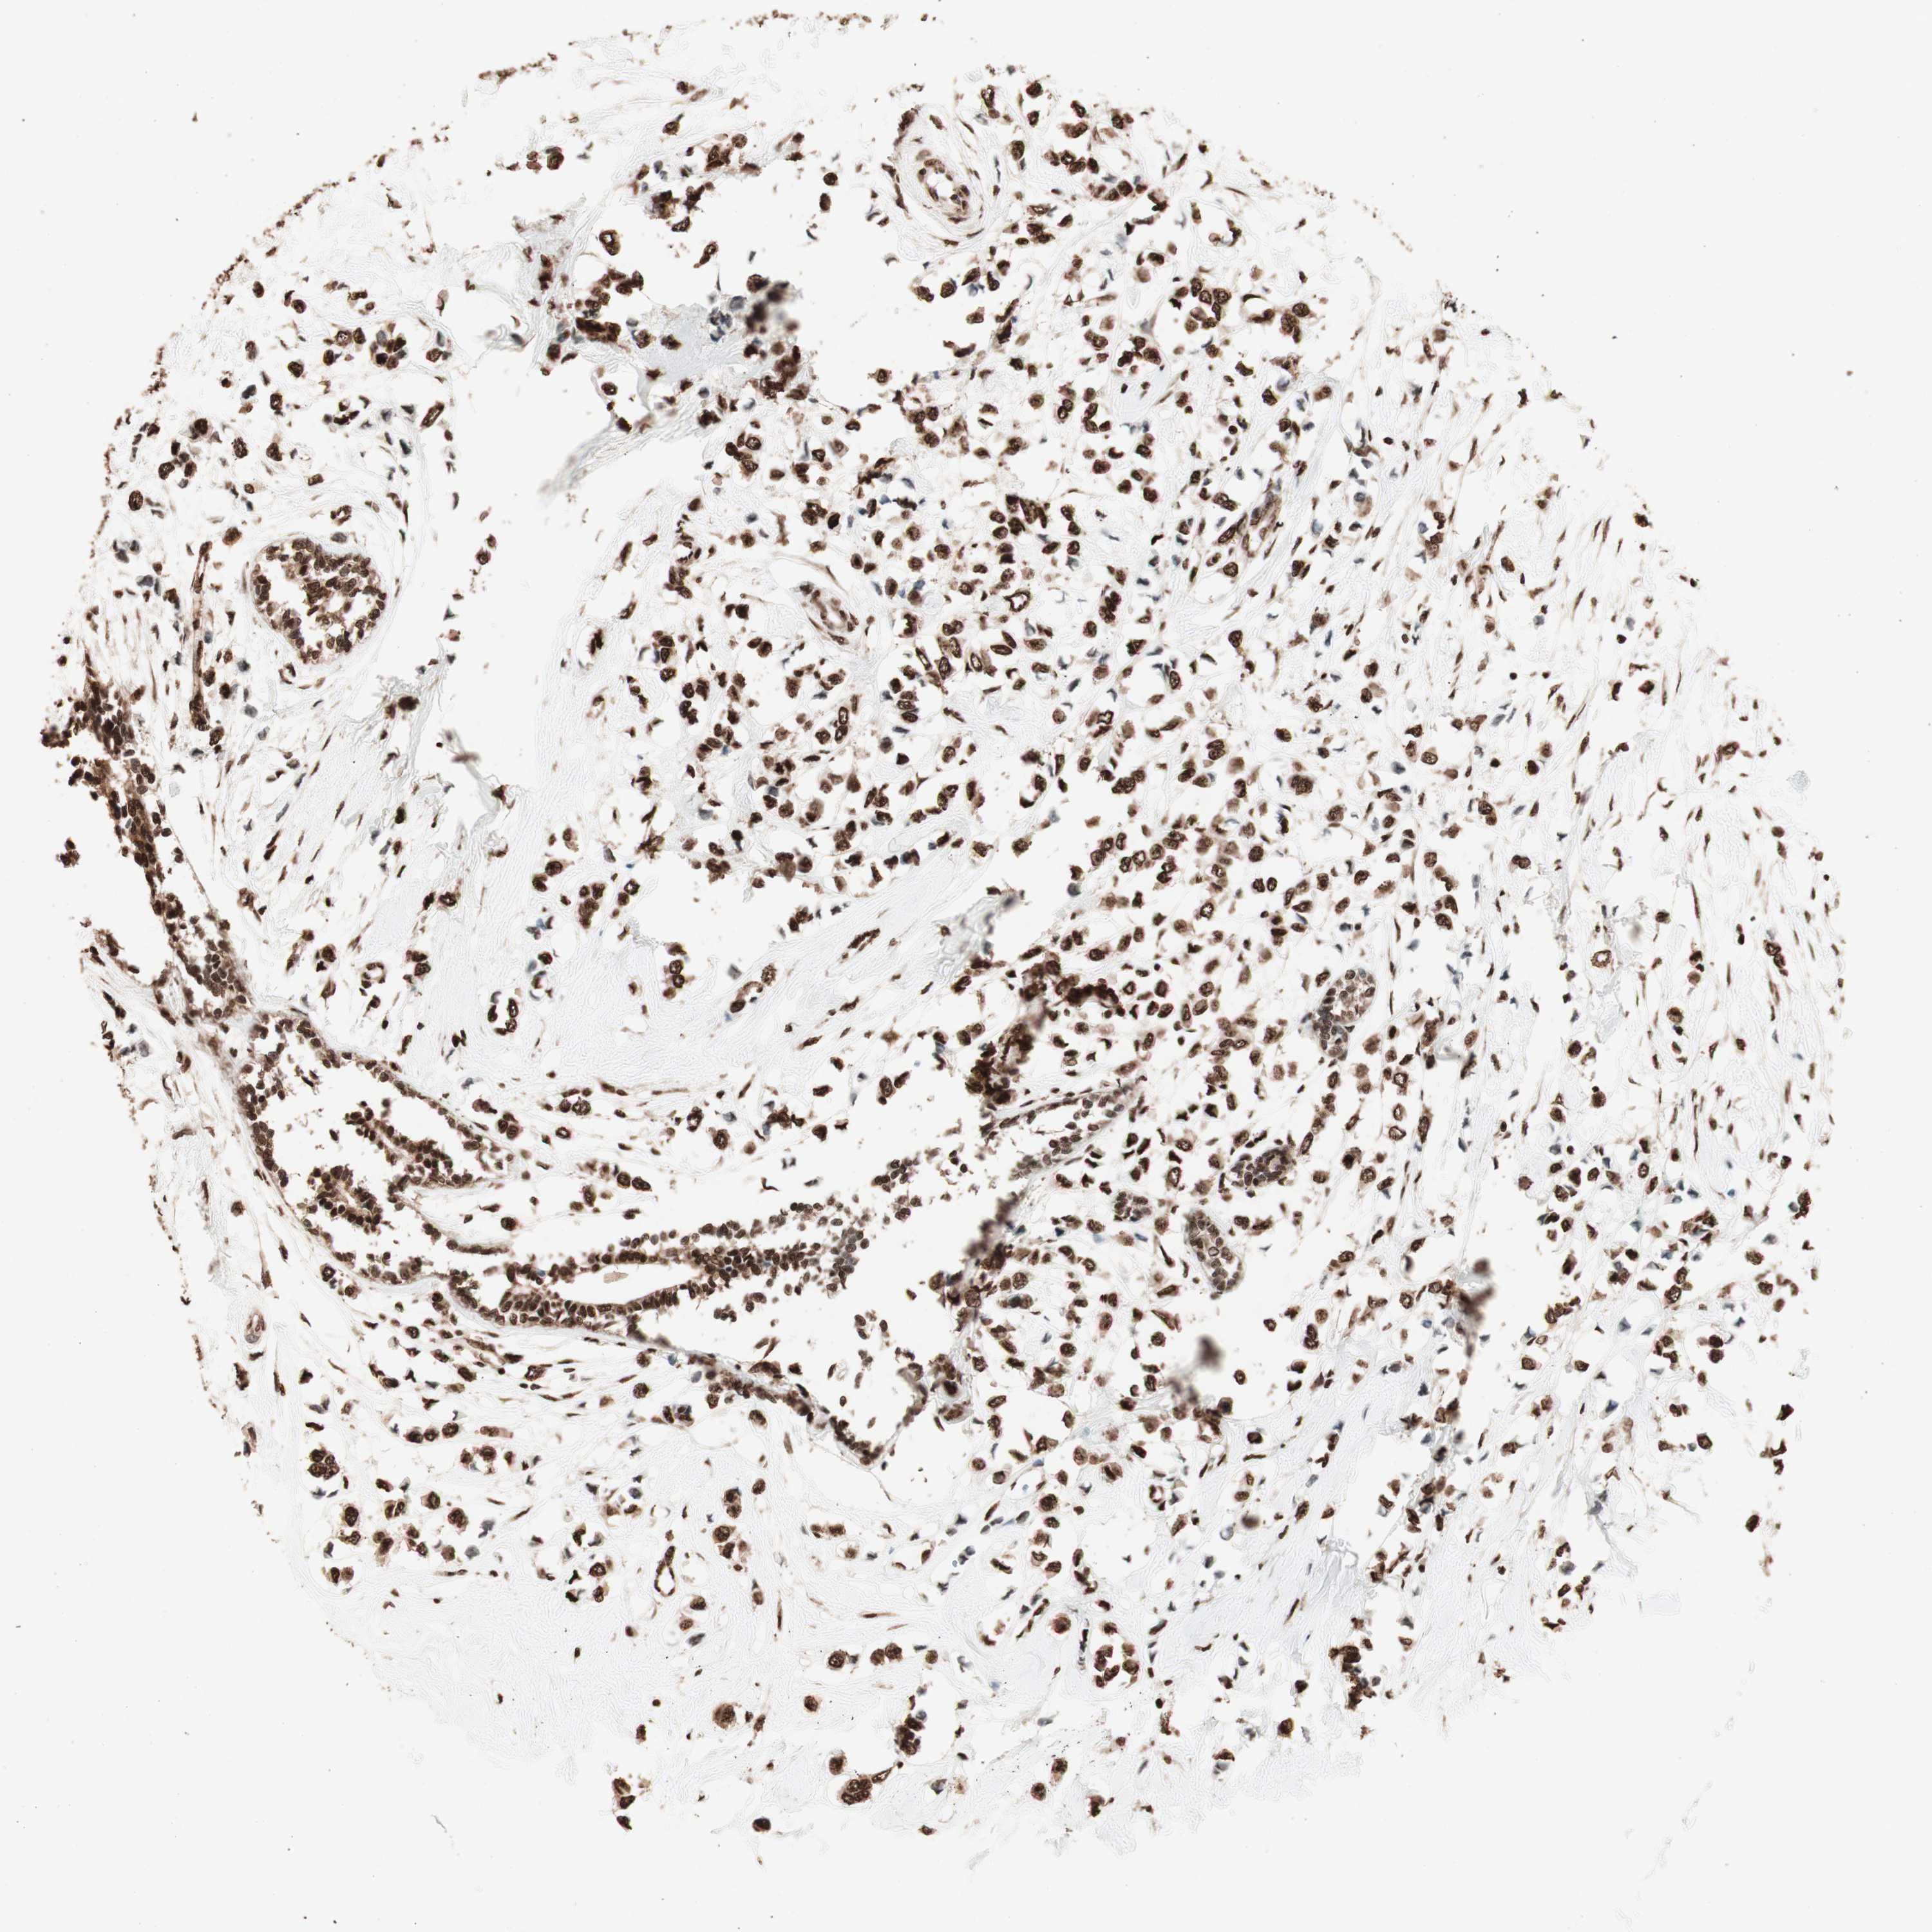

BRCA TCGA BRCA VALIDATION PROTEIN EXPRESSION

ANTIBODIES

AND

VALIDATION